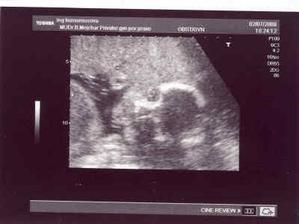

12.3. - první prohlídka v poradně a už jsme dostali těhotenskou průkazku!!! máme další fotečku, kde už miminko vypadá opravdu jako človíček 🙂)

2.4. - podrobný UTZ (screaning v I.trimestru a vše v pořádku hurááá) - mimčo je čiperné, krásně na UTZ skotačí!!!